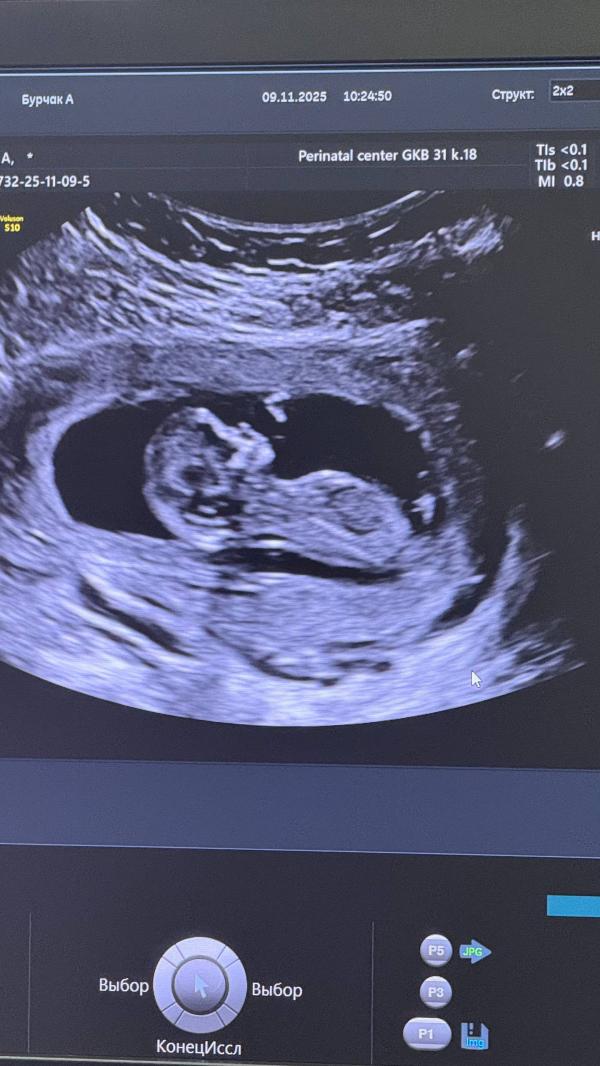

Сходила на скрининг, сказали все хорошо и врач в конце такая у вас похоже мальчик 😄

блин я не планировала узнавать сегодня)) видно бугорок на фото?

Да нуу, не точно) потому что половые органы ещё не сформировались

Обычно на 19-20 недели четко видно

А то что торчит это может быть пуповина

Давайте я сравняю Ваши ожидания: похоже, у Вас девочка 😁 так что, ждите Новогоднюю ночь спокойно, тогда откроется истина 😀

по фото не видно ни одного, ни другого)